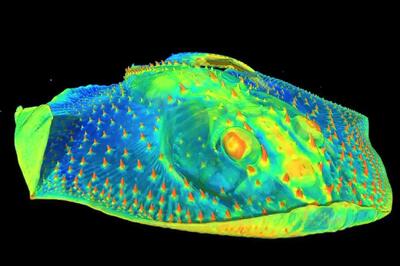

ترمیم معجزهآسای مینای دندان بدون درد و دکتر!

دانشمندان کالج کینگز لندن کشف کردند که کراتین موجود در مو و پشم میتواند به صورت طبیعی مینای دندان را ترمیم کند و جلوی پوسیدگی را بگیرد. یک نوآوری که میتواند انقلابی در مراقبتهای دندانی ایجاد کند.